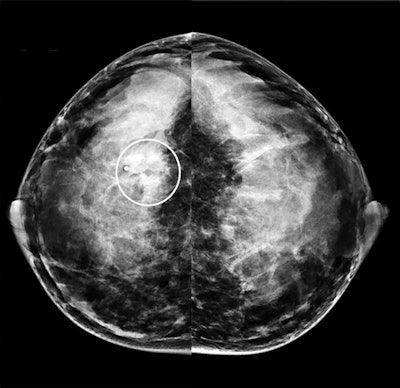

The authors attributed mammography's lower specificity due to the modality's struggle depicting cancers in dense breast tissues during pregnancy and lactation. Notably, 98% of the patients in the study had dense breast tissue, including 72% of whom had extremely dense breast tissue.

"These findings suggest that sensitivity of mammography is slightly limited and inferior to that of [ultrasound] during pregnancy and lactation because of increased breast density," wrote the authors, led by Dr. Maggie Chung from the department of radiology and biomedical imaging at the University of California, San Francisco.